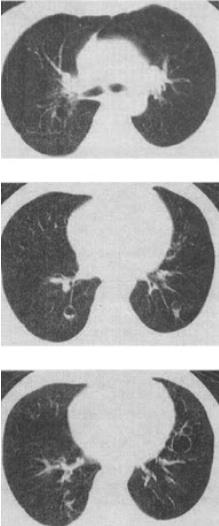

患者女,23岁,咳嗽咳痰反复发作,根据CT图像,最可能的诊断是()。

A、支气管扩张并感染

B、多发肺气囊

C、多发性肺囊肿并感染

D、多发性肺脓肿

E、大叶性肺炎

C